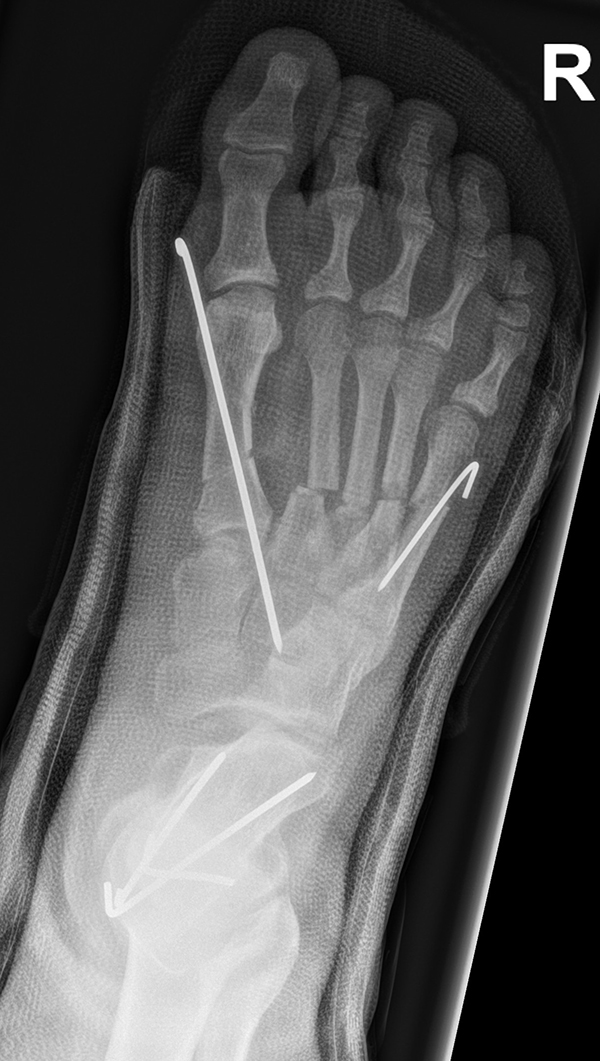

Abb. 36 a-b: Röntgenbild mit allen zuvor beschriebenen Osteotomien und der zusätzlich durchgeführten Metatarsale V Osteotomie in d. p. (dorso-plantare) Ansicht und schräge Röntgenaufnahme.

Zum Lesen der Bildbeschreibung und zur Vollansicht bitte die Bilder anklicken. Bilder: A. Helmers.